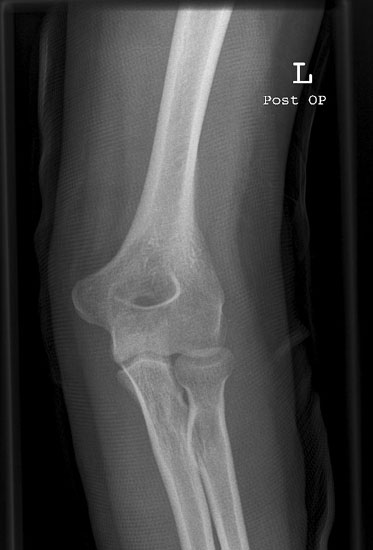

Ellenbogen a.p.

11_2.jpg

Fehler

Der Gelenkspalt zwischen Humerus und Radiusköpfchen ist nicht frei; die Gelenkfläche des Radiusköpfchen ist stark oval gezeichnet und verdeckt die Gelenkfläche des Humerus. Der Patient kippte den Vorderarm mit der Hand hoch statt sie flach aufzulegen.

Abhilfe

Es müssen Vorder- und Oberarm streng gestreckt gehalten werden.